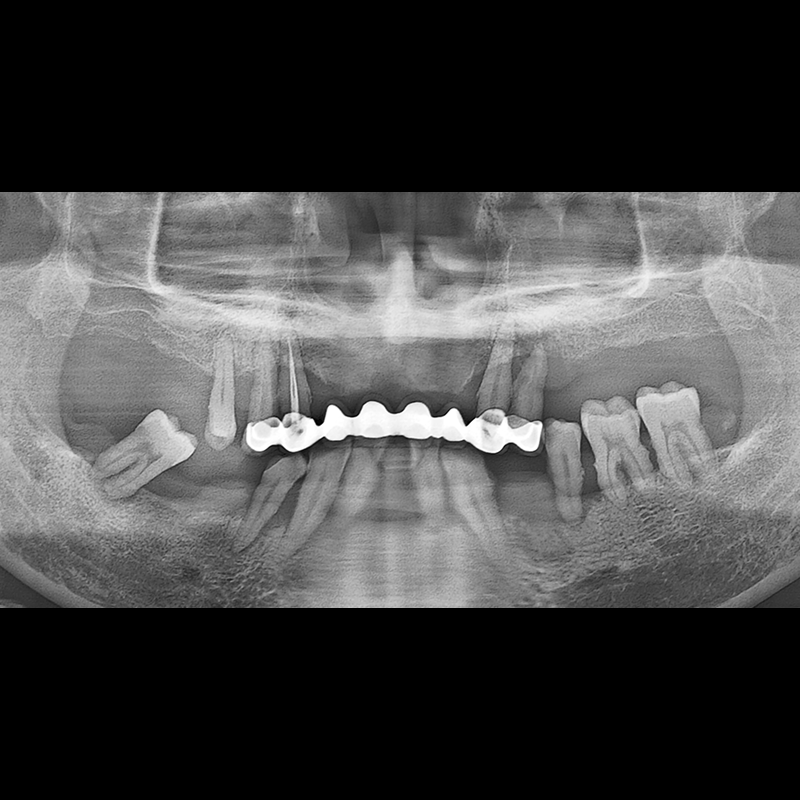

IMPLANT

BEFORE AFTER

インプラント手術事例 2025.05.30

欠損した歯の部分と、生かしにくい歯の位置にインプラントを植立しました。